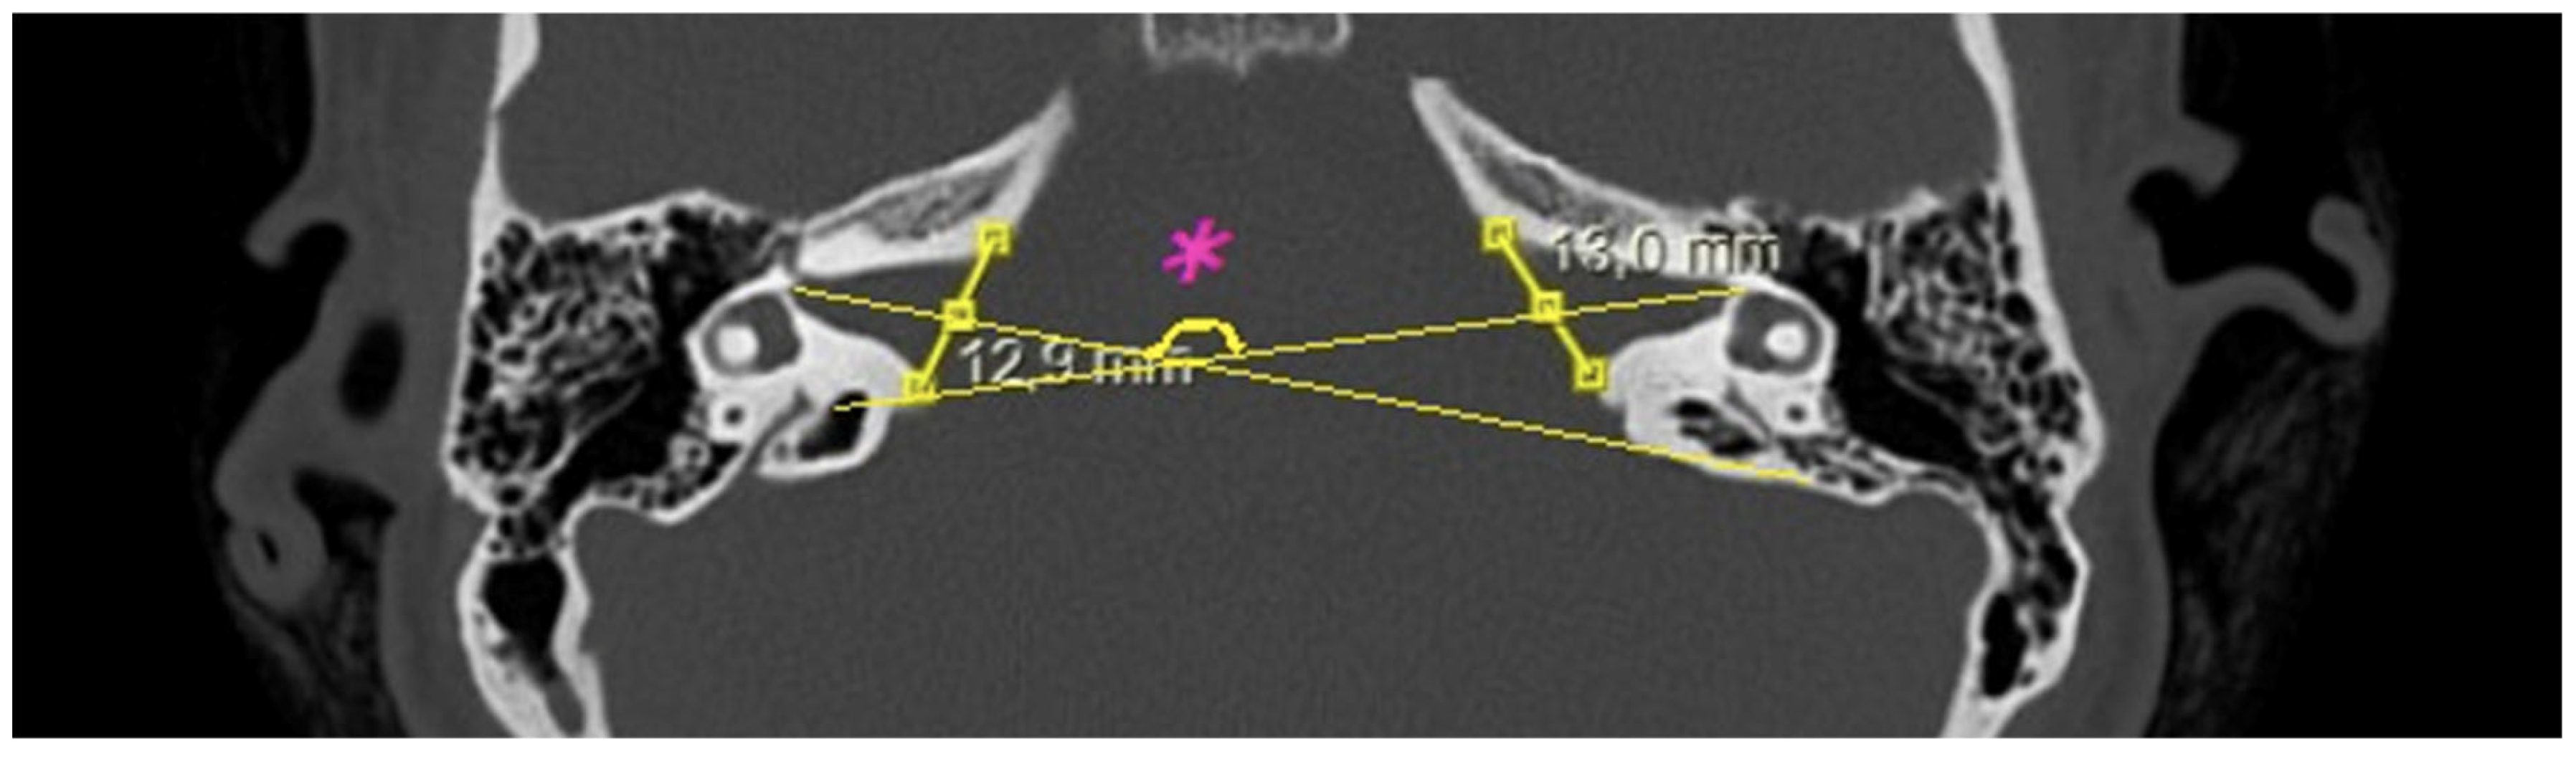

- IAM orientation: the angle formed between the long axis lines passing through the midpoint of the inlet of each IAM (Figure 4).